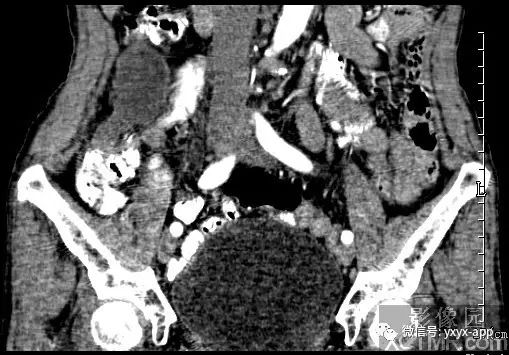

【病史临床】女性,66岁,右下腹胀痛不适一月。

CT影像表现:右下腹囊性肿块,囊液密度均匀,囊壁规整,增强囊壁有强化,周围肠腔无梗阻征象,考虑阑尾粘液囊肿或肠系膜囊肿。

最后结果:手术病理:阑尾粘液囊肿。

B超在阑尾粘液囊肿者可显示具有内回声的囊性肿物,囊壁变薄,且囊壁上有钙盐沉积,在腹膜假粘液瘤者可显示为粘液样腹水回声。CT在粘液囊肿可显示为右下腹包裹较好的壁薄囊性肿物。